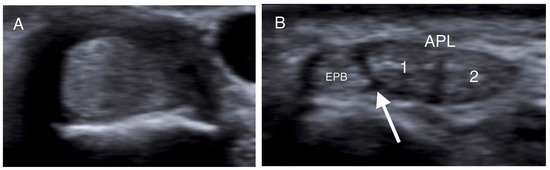

2.3. US Imaging

- Choi, S.J.; Ahn, J.H.; Lee, Y.J.; Ryu, D.S.; Lee, J.H.; Jung, S.M.; Park, M.S.; Lee, K.W. De Quervain Disease: US Identification of Anatomic Variations in the First Extensor Compartment with an Emphasis on Subcompartmentalization. Radiology 2011, 260, 480–486. [Google Scholar] [CrossRef]

- Kwon, B.C.; Choi, S.J.; Koh, S.H.; Shin, D.J.; Baek, G.H. Sonographic Identification of the Intracompartmental Septum in de Quervain’s Disease. Clin. Orthop. Relat. Res. 2010, 468, 2129–2134. [Google Scholar] [CrossRef]